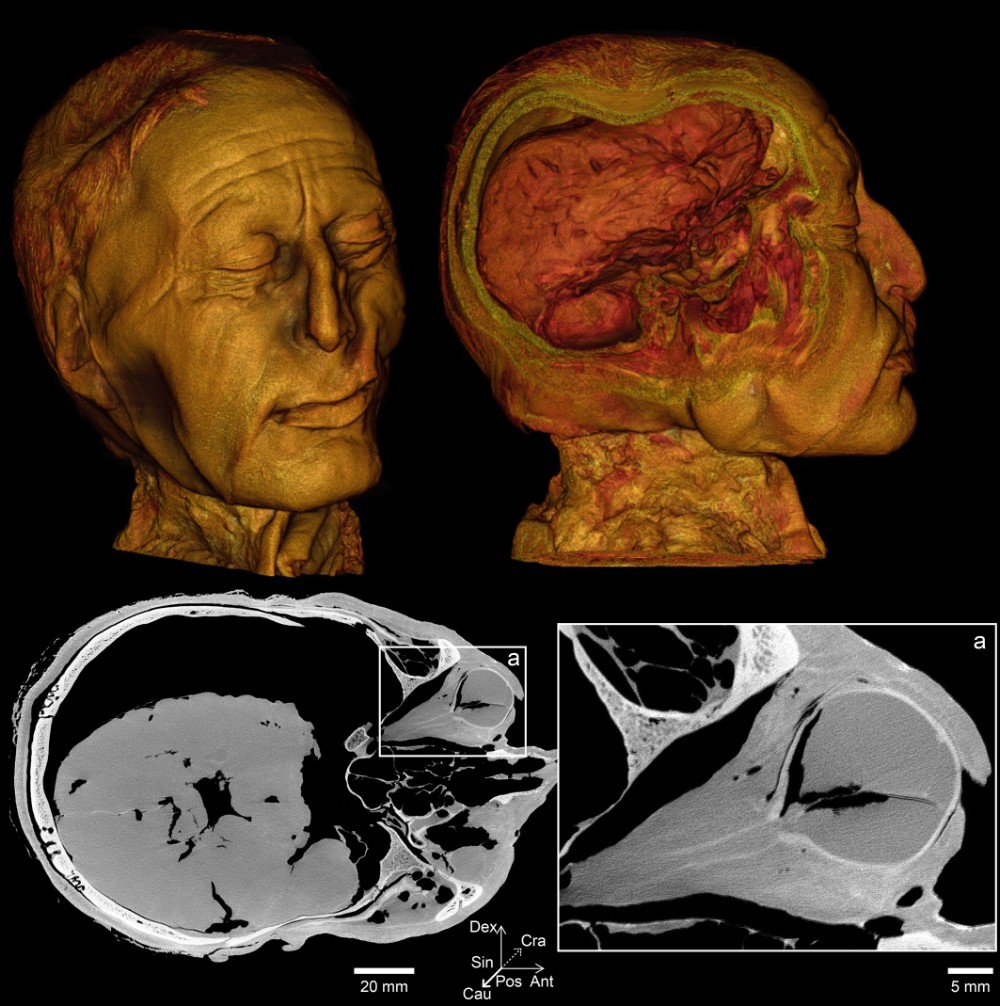

Det lyder som noget fra en krimi, men der var dog ikke noget lyssky over det. Det var nemlig Museum Silkeborgs forskningschef Nina Helt Nielsen, konservator Lars Vig Jensen og direktør Ole Nielsen, der stod for aktionen, hvor Tollundmandens hoved blev kørt fra Museum Silkeborg til Institut for Retsmedicin på Aarhus Universitet. Her gennemgik det berømte hoved grundige undersøgelser i både en klinisk CT-scanner og i universitetets nye mikro-CT-scanner, som kan tage billeder med meget stor detaljegrad.

De billeder vi indtil videre har set, har været ualmindeligt detaljerede. Bl.a. kan vi nu se Tollundmandens tænder og øjne, som ikke kan ses udefra, fordi både mund og øjne er lukkede. Det ene øje ser oven i købet ud til at være fuldstændig intakt med form og synsnerver , og det er helt fantastisk. Hvad er chancerne lige for at noget så skrøbeligt som et menneskeligt øje overlever i en mose igennem 2400 år.

Hovedet har været scannet én gang før – i 2002. På de gamle scanninger kunne man kun se tænderne som utydelige pløkker. Opløsningen i de nye billeder er 422 gange bedre end i de gamle. Det gør en forskel.

De nye scanningsbilleder er så flotte på grund af den gode kontrast, som gør det nemt at se forskel på forskelligt væv. Da Tollundmanden har ligget i en syrlig mose i 2400 år, er meget af hans knoglemineral udvasket. Derfor er kontrasten mellem knogler og det bløde væv mindre end normalt. Men på en mikro-CT-scanner kan opnå bedre kontrast på de forskellige væv og se mange flere detaljer.

Den nye scanner adskiller sig fra universitets andre mikro-CT-systemer, fordi den både kan scanne små prøver ved ultrahøj opløsning og producere billeder af store genstande – som et helt hoved fra et oldtidsmenneske.